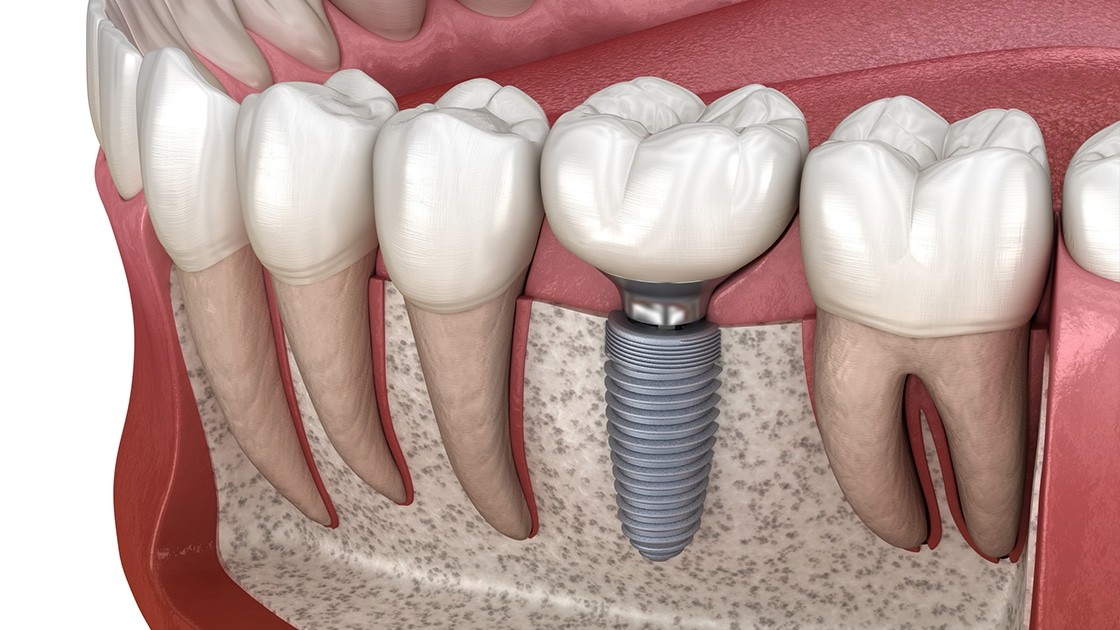

Аноним 24/07/25 Чтв 03:52:58 #14 №1633058

Блять, пару лет назад когда ставил имплант на 5 зуб, мне врач сказал чтобы я удалял нахуй нижнюю восьмёрку, иначе пизда будет рано или поздно. Ну а я хуй забил разумеется.

И это произошло на прошлой неделе. Сначала нестерпимая боль на ночь глядя, всякие ибупрофены не помогли. В итоге бессонная ночь и дикий ахуй утром. Ещё и температура скакать начала. Работать не смог, побежал по стоматологиям.

В самой первой из них мне сказали, что дескать тут отёк, давай-ка ложись в ЧЛХ, при этом направления разумеется не выписали, сам ебись - пидоры блять.

Подумал, что направление дадут в муниципальной областной стоматологии, побежал туда. Там меня отфутболили, сказав что зашиваются и иди нахуй. Но дали наводку на частную клинику, которая может работать с ОМС по острой боли и направления тоже выписывает.

Побежал вприпрыжку туда, а степень охуения от боли и ебейший недосып - заставили меня скулить. Там меня впервые за день нормально принял врач, ничего не стал говорить про ЧЛХ. Я тут возрадовался, что меня могут и локально починить, удалив эту ебаную 8ку. Но удалять сразу не стал, опять же сказал что отёк. Вместо этого прописал всякие антибиотики и противовоспалительные, мол как отёк снимется, приходи, удалим. А если вдруг на следующий день отёк станет ебовый, немедля беги на приём.

Ну я въебал прописанные пилюли, даже немного полегче стало. Но проснулся с ебалом в 3 раза большим, чем днём ранее. Общее состояние нестояния, температура, хуевое самочувствие, всё болит, полный пиздец. Где-то к обеду я кое как взял себя в руки и побежал к этому стоматологу. Он покачал головой и немедля выписал направление. Флегмона, абсцесс.

Через часик уже был в приёмном покое больницы. Буквально в первые полчаса как меня положили, мне разрезали слизистую под щекой, чтобы хоть как-то убрать воспаление, поставили дренаж. Это было довольно больно, потому что восьмерка ретинированная, там скапливался гной и обезбол действовал так себе. Потом через пару дней, когда отёчность более менее сошла и я мог открывать рот примерно на ширину двух сложенных пальцев, мне удалили 8ку с пилением кости. Она у меня росла по ебанутому ещё - вбок, но какбэ наоборот, корнями в сторону 7ки. Практически все эти дни я был на обезболе, который кололся в жопку по желанию. Лишь в предпоследний день перед выпиской я более менее комфортно себя мог ощущать без обезбола. Выписался пару дней назад и вот сегодня боли вообще практически не беспокоили. Изредка боль может пробить в ухо, но это хуйня.